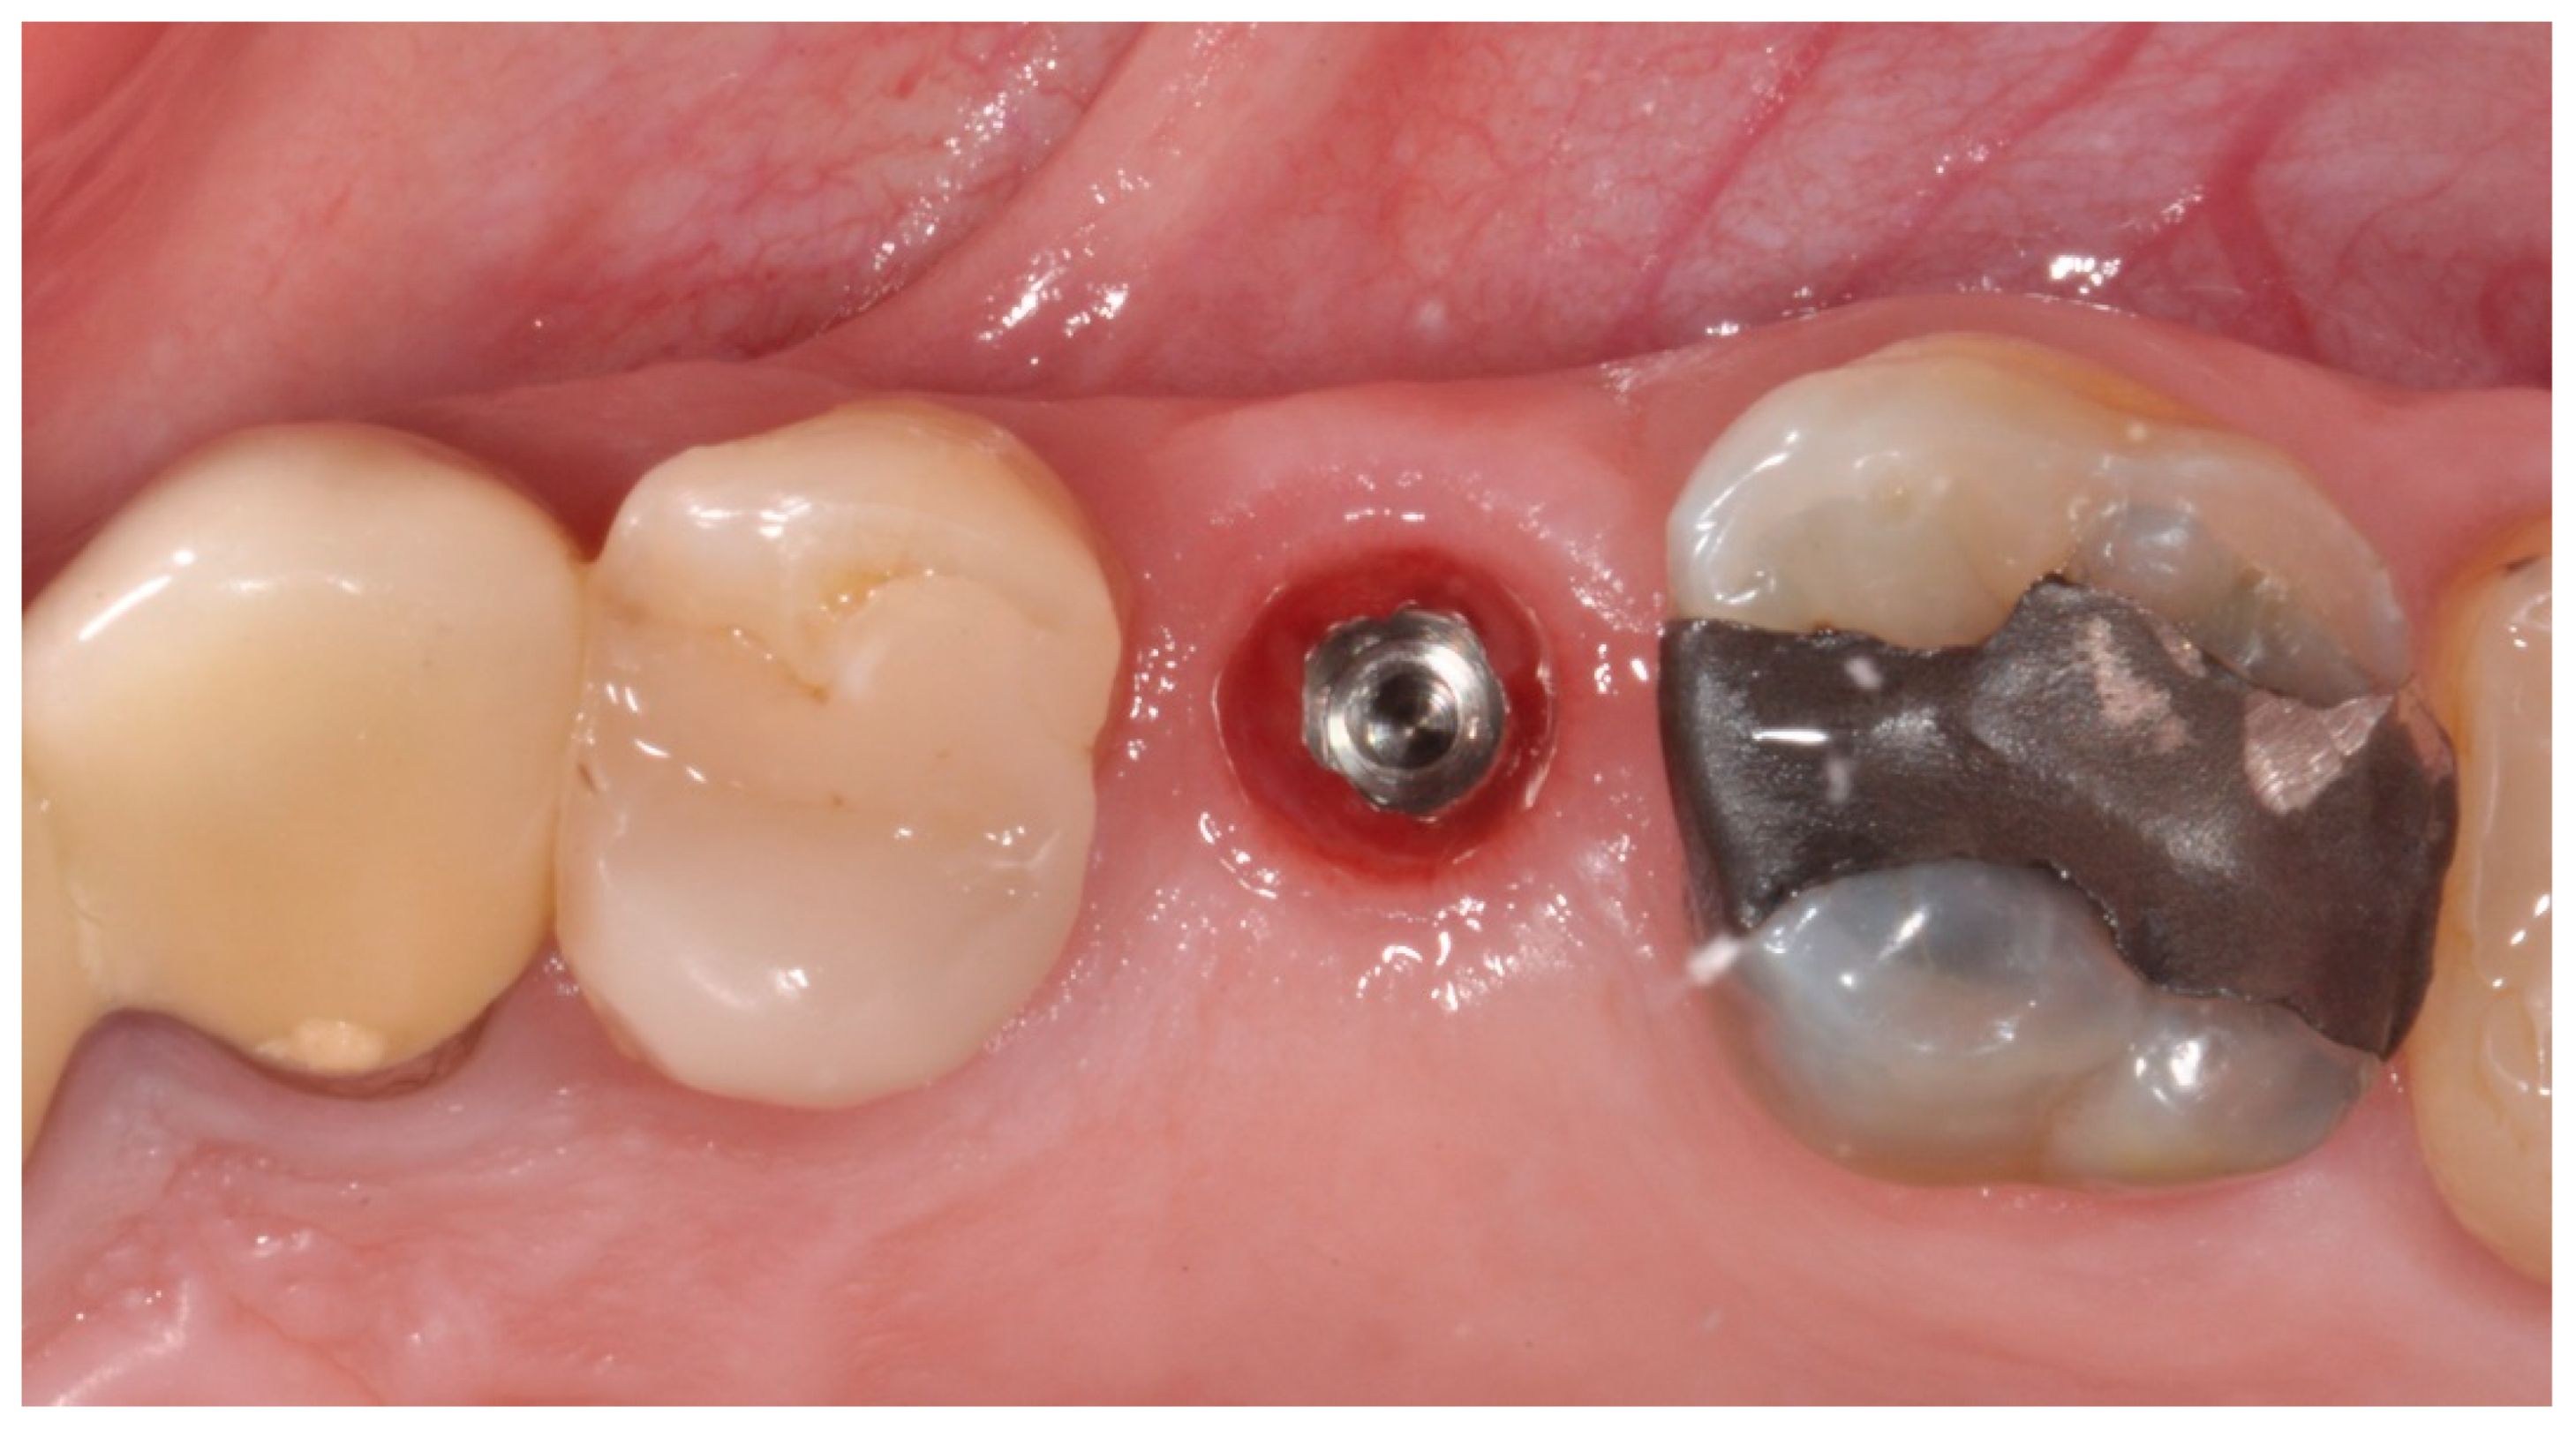

2.2. Surgical Procedures

2.3. Prosthetic Protocol